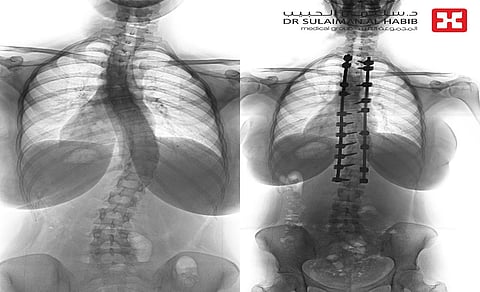

وقال د. خليفة إن المريضة راجعت المستشفى، وهي تشتكي من انحناء جانبي للعمود الفقري منذ نحو سنة، ومؤخرًا تزايدت حدة الأعراض، وأصبحت تعاني من صعوبة في ممارسة الحياة الطبيعة، وتغير نمط حياتها وتقيدت حركتها.. وفور وصولها إلى المستشفى أجريت لها التحاليل والفحوصات الطبية الدقيقة، التي بينت إصابتها بحالة انحراف "جنف" بدرجة "43" بالفقرات الصدرية، ودرس الفريق الطبي الحالة على ضوء نتائج الفحوصات والتحاليل، وخلص إلى ضرورة التدخل الجراحي لعلاج العيوب، والحد من المضاعفات.

وأخضعت الشابة لعملية جراحية، تم فيها تقويم العمود الفقري بعدد 20 من البراغي والقضبان المعدنية والطعوم العظمية الصناعية، وتثبيت ودمج الفقرات، وشارك في العملية التي استمرت لـ"4" ساعات، فريق تخدير متمرس، وفريق تمريضي ماهر، كما استخدم فيها جهاز الملاحة العصبية، إضافة الى مجموعة من أحدث الأجهزة الطبية التي ساهمت مع الكوادر الطبية عالية الكفاءة والتأهيل بالمستشفى في إنجاحها.